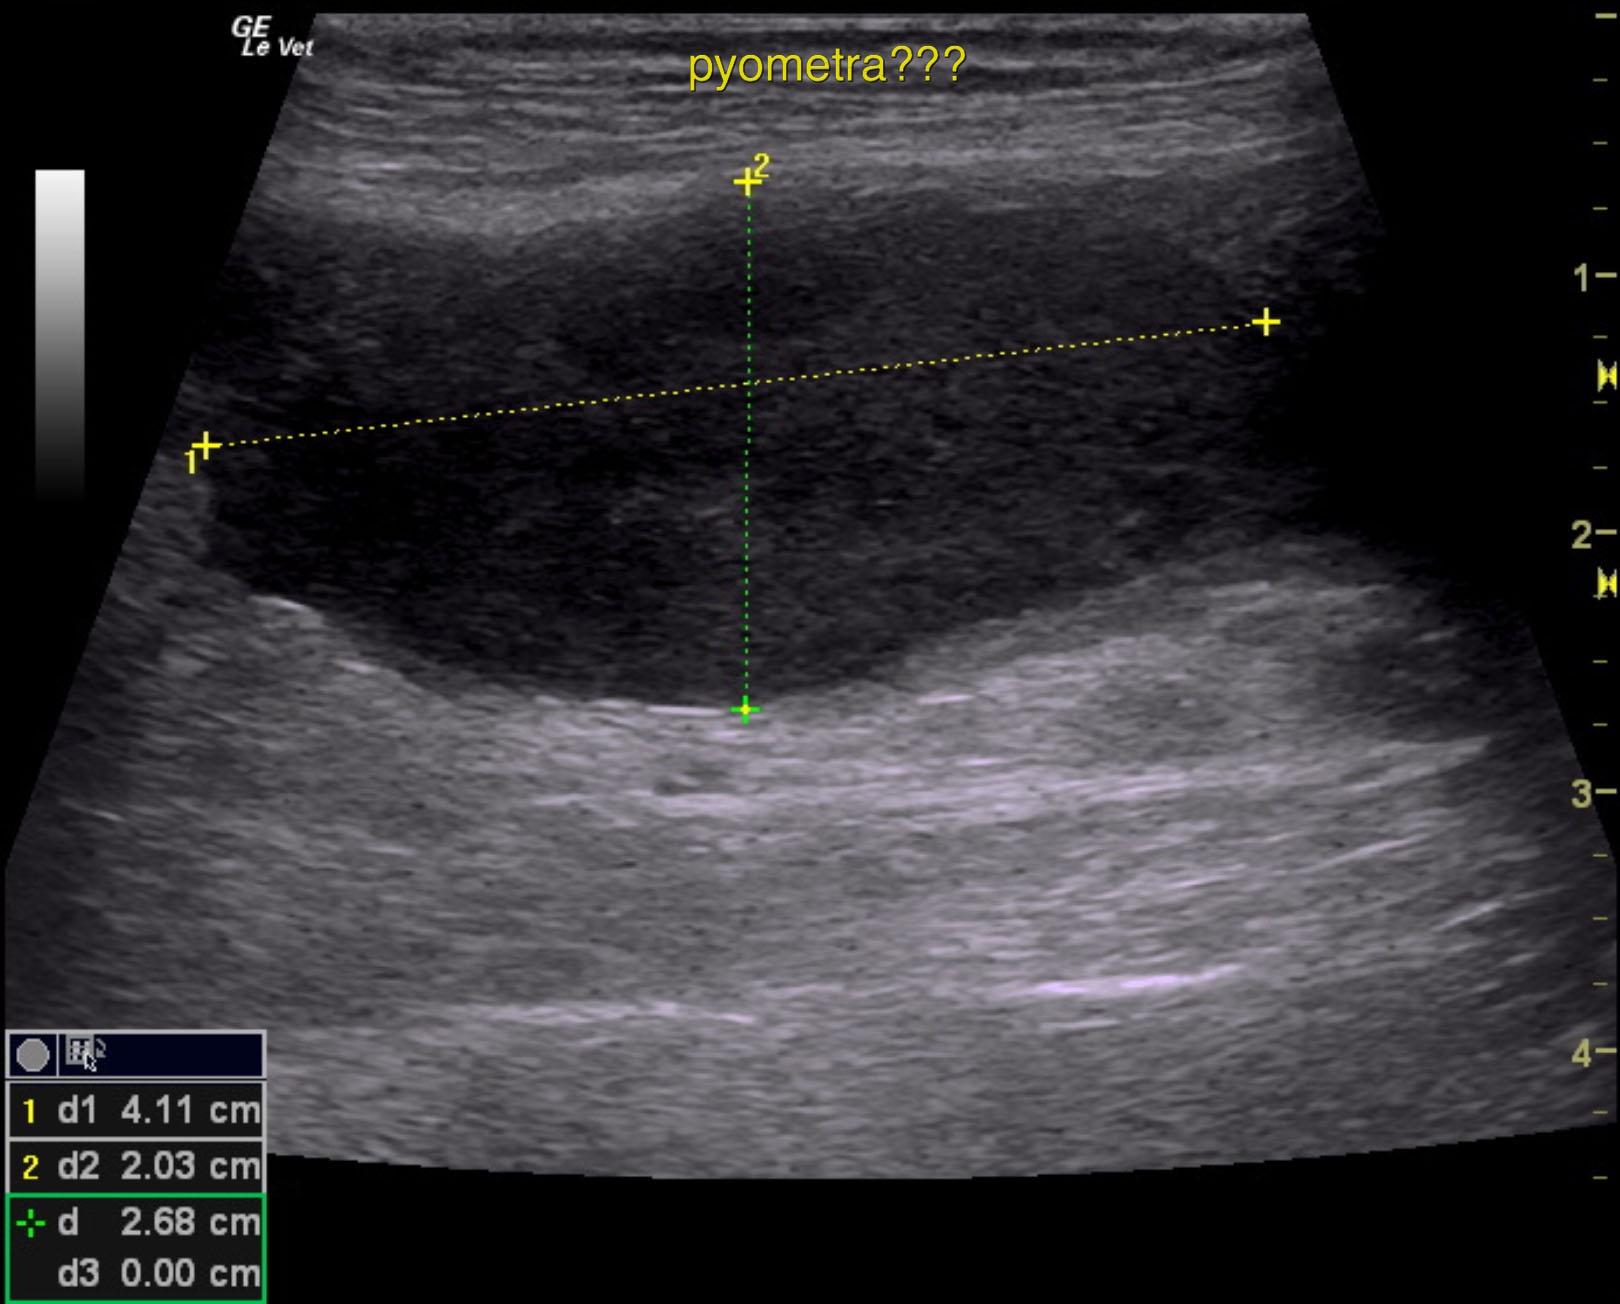

Tubular structure in the pelvis region.

The urinary bladder itself presented minor thickening and minor debris. A tubular structure was noted in a position between the colon and the urinary bladder with dilation.

Purulent material was obtained on ultrasound-guided centesis without complications. However, reactive mesentery was noted throughout the pelvis. The position of this tube would fit with a uterus. This patient may be a hermaphrodite with secondary pyometra. I cannot make a direct connection from the tubular structure to the prostate itself as they appear to be separate. I recommend exploratory surgery with removal of this structure. The ureters do not appear to be involved. The position and structure would be that of a uterus. Therefore, treatment for pancreatitis and localized infection in the region of the pelvis would be recommended with IV fluid support, broad spectrum antibiotics such as Enrofloxacin and Clindamycin combination as well as exploratory surgery. If the tubular structure is confirmed to be a uterus and hermaphroditism then examination for possible ovaries would also be warranted even though none were visible in the image set. Regardless, this tubular structure necessitates surgical resection.